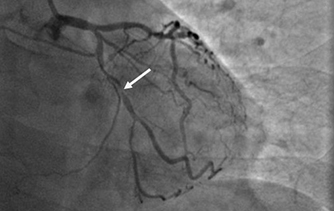

近日,河北醫科大學附屬燕達醫院心血管內三科成功完成一例非常特殊的手術——冠心病三支病變微創介入完全血運重建術?;颊呃钕壬谛牟〔∽儤O其嚴重,全部三支主干動脈均重度狹窄,各處求診均被告知無法微創介入手術,只能開胸搭橋。拒絕開胸的李先生慕燕達醫院心血管內三科北京安貞醫院專家團隊之名,就診于燕達醫院,由翟光耀主任為其行 “一站式”手術,一 次 性完成三支動脈的修復!手術非常成功,李先生術后恢復良好,滿意出院。   震驚 患者三支血管均90-99%狹窄 ..